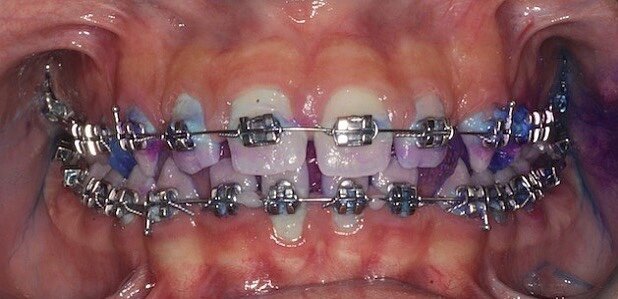

Di fatto i pazienti del gruppo I hanno riscontrato miglioramenti significativi rispetto al gruppo II, nel tempo di follow-up (Figg. 1, 2). Conclusione Prendendo in considerazione l’analisi statistica si può affermare che nella terapia di mantenimento durante il trattamento ortodontico, il dentifricio Biorepair Peribioma costituisce un valido alleato nel mantenimento dell’equilibrio microbico e della salute orale. Ruolo fondamentale nella sperimentazione è quello dell’istruzione e motivazione del paziente alle corrette manovre di igiene orale domiciliare, influenzando così il miglioramento generale degli indici. Ampiezza del campione e durata della sperimentazione costituiscono un limite dello studio, che sarà continuato e approfondito nel tempo per valutare gli effetti a lungo termine.

Fig. 1 - Case report di ortodonzia tradizionale. Fotografia frontale a t0 con rilevatore di placca.